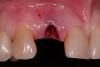

After placement of the surgical guide, the initial site coring was accomplished (Figure 5). The surgical site was widened to 2.8 mm in diameter and 13 mm in length. A Zimmer® (Zimmer Dental) 3-mm x 13-mm one-piece implant was then seated into the previously made osteotomy site (Figure 6). A facial osseous defect existed on the facial of the implant surface, by loss of the facial plate (Figure 7). An allogenic graft, Puros® large-particle cancellous mineralized chips (Zimmer Dental), were placed into the facial defect to obliterate the void on the facial of the implant surface (Figure 8). Once the grafting procedure is accomplished, the provisionalization procedure was started.

Figure 6  One-piece implant seated.

Figure 6